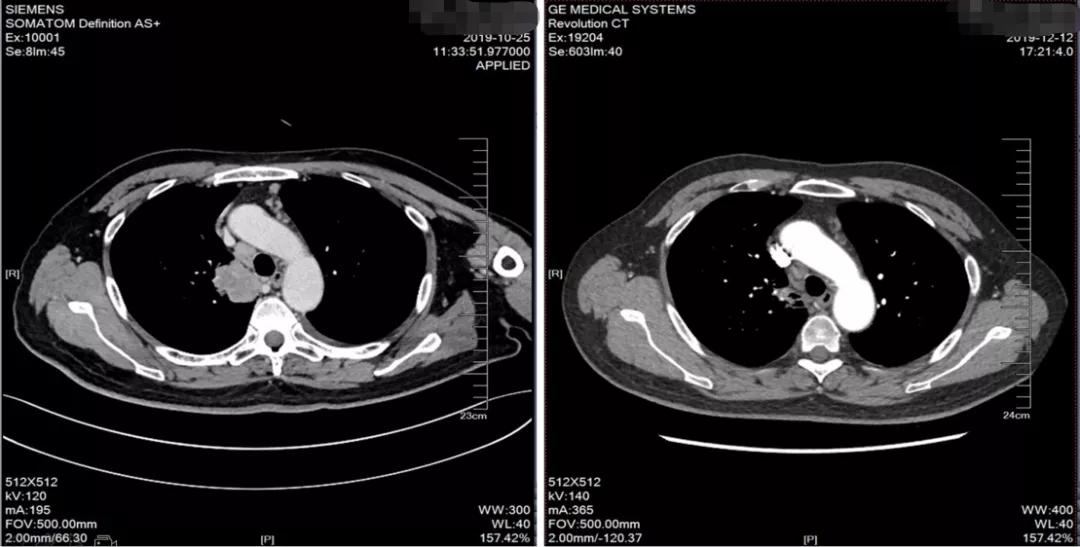

化疗两程后复查

2019-12-12胸部CT示考虑右上肺癌并右肺门及纵隔淋巴结转移,较前缩小

2019-12-12头颅MRI示右侧额叶及左侧顶叶少许缺血灶,未见异常强化影